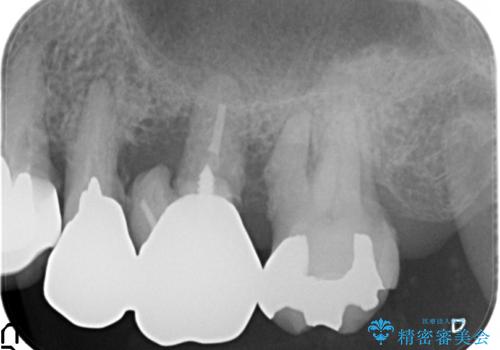

歯ぐきから血が出る、歯ぐきが腫れている 80代女性

- 歯ぐきからの出血と腫れを主訴に来院された患者様です。

プラークコントロールが非常に悪く、全顎的な歯周病に罹患していました。

「抜歯したくない、インプラントは嫌」という患者様のご希望とご年齢を考慮し、可及的な骨外科処置や根分割術によりできるだけ今ある歯を残す治療方針をたてました。

保存不可能な左上の奥歯2本(左上67)は抜去し、ノンクラスプデンチャーをいれることにしました。

歯ぐきの腫れや出血が改善され、喜んで下さいました。

プラークコントロールを徹底して頂き、できるだけ歯が長持ちするよう今後も定期検診でフォローさせて頂きます。

被せ物の種類:メタルボンドクラウン エコノミー

入れ歯の種類:ノンクラスプデンチャー